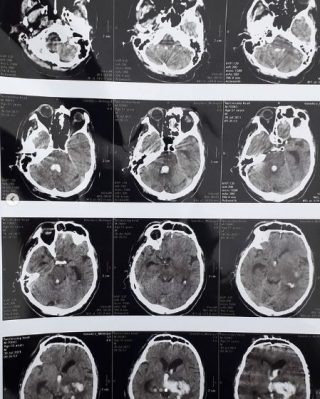

Сергій Валентинович потребує допомоги на лікування геморагічного інсульту (внутрішньомозковий крововилив).